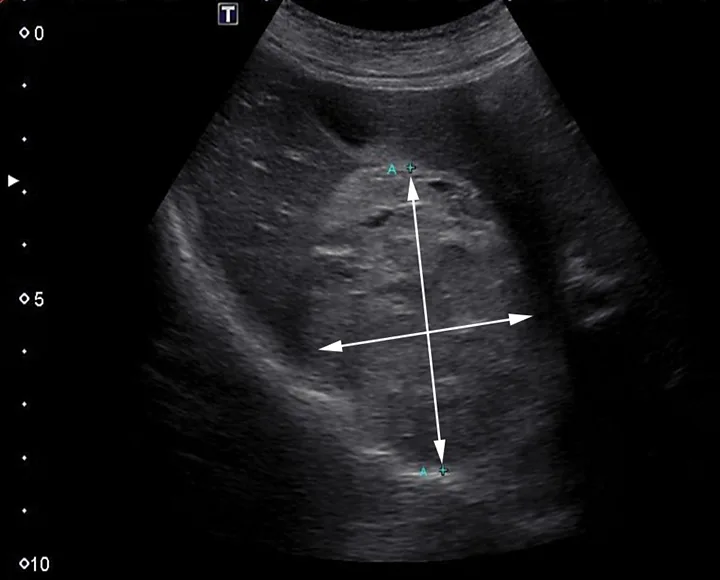

Ultrasonographic appearance of a second hepatic mass measuring 5.7 cm on initial presentation. Area of mass demonstrated by arrows

Mild leukocytosis (17.3 × 103/μL [17.3 × 109/L]; reference range, 4.3-13.6 × 103/μL [4.3-13.6 × 109/L]) and mild regenerative anemia (hematocrit, 33% [reference range, 40%-57%]; reticulocytes, 150 000/μL [150 × 109/L]) were noted. The remainder of the CBC, coagulation profile, and serum chemistry profile were within normal limits. Abdominal ultrasonography demonstrated a large (>10 cm in diameter) hepatic mass (Figure 1) originating from the left aspect of the liver that contained numerous variably sized anechoic regions and mild anechoic peritoneal effusion. Two smaller masses were visible in the hepatic parenchyma (Figure 2). Ultrasound-guided fine-needle aspiration of the large hepatic mass was performed, and cytology showed evidence of previous hemorrhage and mild extramedullary hematopoiesis. Ultrasound-guided biopsies were not considered safe because of the risk for hemorrhage due to the cavitated nature of the masses. The top differential diagnosis was malignant neoplasia (eg, hemangiosarcoma, histiocytic sarcoma, hepatic adenocarcinoma); benign (eg, hemangioma) or infectious (eg, fungal or parasitic) lesions were considered possible but unlikely. Thoracic radiographs were unremarkable.